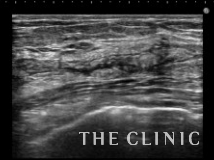

この方は他院でCRF豊胸を受けられました。手術後1年後ぐらいから硬さと違和感を感じ始め、最近は痛みも出現してきたためしこり除去を希望されて当院を受診されました。両側の乳腺下に10㎝を超える大きなしこりを認めます。カプセルに包まれた混合性(充実成分とオイル成分)のしこりです。

左)エコー下にベイザーリポで充実性成分を崩します。

右)カニューレで壊死した脂肪を吸引除去します。

左)吸引後の状態です。カプセルは残っていますが、壊死脂肪はほとんど消失しました。右)除去した壊死脂肪です。

これだけ大きなしこりはカプセル内に液体が貯留する場合がありますが、フォローアップのエコーでは問題ありませんでした。